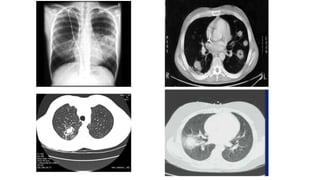

CT: macronodules/ halo sign

Air-crescent sign

Cavity